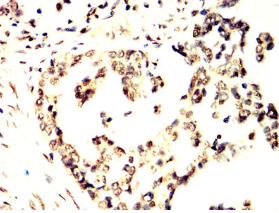

TCF7 Mouse Monoclonal antibody[1B4E9]

This gene encodes a member of the T-cell factor/lymphoid enhancer-binding factor family of high mobility group (HMG) box transcriptional activators. This gene is expressed predominantly in T-cells and plays a critical role in natural killer cell and innate lymphoid cell development. The encoded protein forms a complex with beta-catenin and activates transcription through a Wnt/beta-catenin signaling pathway. Mice with a knockout of this gene are viable and fertile, but display a block in T-lymphocyte differentiation. Alternative splicing results in multiple transcript variants. Naturally-occurring isoforms lacking the N-terminal beta-catenin interaction domain may act as dominant negative regulators of Wnt signaling.

Immunogen:    Purified recombinant fragment of human TCF7 (AA: 168-358) expressed in E. Coli.

IHC    1/200 - 1/1000